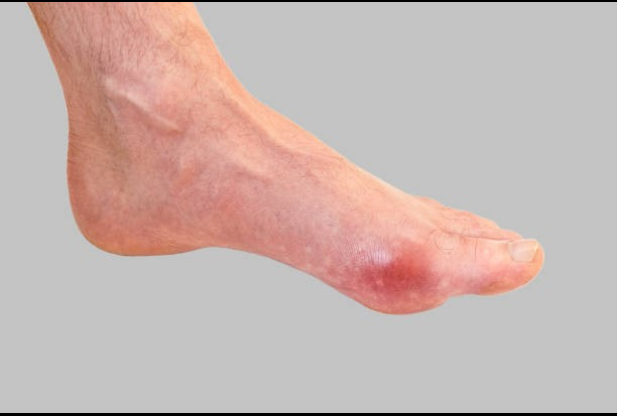

그 후, 손, 무릎, 발목의 관절에 계속해서 영향을 줄 수 있습니다. 통풍의 증상은 시기에 따라 고요산혈증, 급성 통풍성 관절염, 간헐성 통풍의 3단계로 분류할 수 있습니다. 일반적으로 엄지발가락 관절의 갑작스러운 종창이 처음 징후이며, 곧 해당 부위에 극심한 통증과 발적이 뒤따릅니다. 관절이 뜨거워져 신발을 신을 수 없게 될 수 있습니다. 그리고 손, 무릎, 발목의 관절에도 연속적으로 영향을 미칠 수 있다.

통풍이 진행된다면 10일 정도 지속되며 완화되더라도 재발하거나 악화될 수 있으므로 치료를 받아야 합니다. 급성 통풍성 관절염은 보통 엄지발가락에 나타나지만 발 관절, 발목, 무릎, 심지어 손목에도 영향을 미칠 수 있습니다. 간헐성 통풍은 일반적으로 6개월에서 2년 사이에 2번째 발작을 일으킵니다. 통풍 발작을 치료하지 않으면 시간이 지남에 따라 여러 관절로 전이될 가능성이 높아지므로 반드시 치료를 받고 정상적인 요산 수치를 유지해야 합니다.